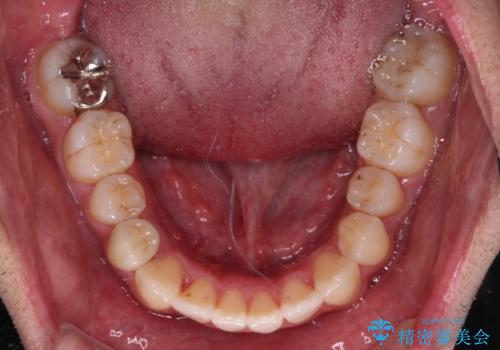

- 前歯のデコボコとクロスバイトを気にして来院された患者様です。

下顎の歯列弓に対して上顎歯列弓がやや小さく、側方の歯を中心にクロスバイトが見受けられました。

クロスバイトの改善は、インビザラインの場合歯髄壊死のリスクや咬み合わせが改善しきらないリスクがあるため、ワイヤー矯正をお勧めすることが多いですが、患者様の希望によりインビザラインにて矯正治療を行うこととしました。

後方に隠れていた上顎前歯は矮小歯であるため、矯正治療の途中でオールセラミッククラウンを装着し、左右対称の大きさでの仕上がりを目指すこととしました。

奥歯の咬み合わせは接触が少なく物足りないように見えますが、患者様としては十分に咬むことができるとのことでした。